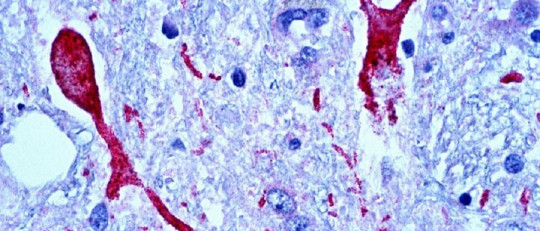

Investigaciones científicas han demostrado que las personas que practican la generosidad de manera regular experimentan beneficios significativos para su bienestar emocional. Al realizar actos generosos, se desencadenan reacciones neuroquímicas positivas en el cerebro, como la liberación de endorfinas, conocidas como las "hormonas de la felicidad". Este fenómeno contribuye a una mejora en el estado de ánimo y a la reducción del estrés.

La generosidad también se asocia con la liberación de oxitocina, la "hormona del amor", que desempeña un papel vital en la formación de vínculos afectivos y la reducción de la ansiedad social. En resumen, ser generoso no solo beneficia a quienes reciben, sino que también actúa como un potente impulsor de la salud mental individual al desencadenar respuestas neurobiológicas positivas.